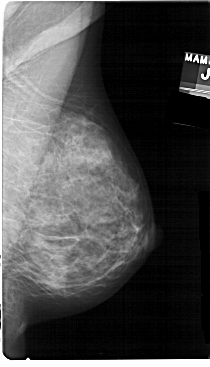

A_1392_1.RIGHT_CC

RIGHT_CC LINES 5041 PIXELS_PER_LINE 2716 BITS_PER_PIXEL 12 RESOLUTION 43.5 NON_OVERLAY